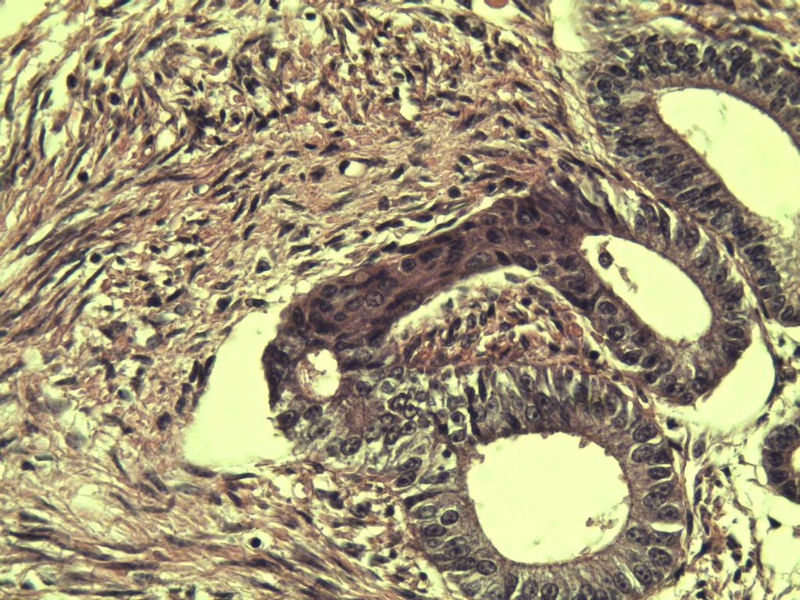

42岁 月经不规则一年 b超发现子宫肌瘤 行全子宫切除术  我取材时发现子宫颈管上段有一质地较硬区 2*1cm  请各位老师看看 是子宫内膜癌不? 谢谢了!

这是子宫颈管上段

子宫颈管上段图1

非癌,考虑子宫内膜异位症或腺肌瘤

肌层内腺体的特点:1、无内膜间质。

2、有鳞化。

3、无异型。所以应该还是个良性病变

非典型性息肉样腺肌瘤。

诊断依据:

1.临床特征:主要发生在绝经前女性,中位年龄39岁,大多数伴有月经紊乱。

2.大体特征:最常见于子宫下段,平均大小为直径2cm,表现为圆形,凸出于表面。息肉样的本质不总是很明显,也有无蒂和广基的肿瘤。

3.镜下特征:上皮成分由杂乱无章排列的不规则的子宫内膜型腺体构成,可以是立方形到矮柱状或假复层。显示有广泛的鳞化区域(本例图11-17均显示鳞化),表现为圆形的“桑葚”(图16-17);间质主要由平滑肌构成,且混有纤维组织。